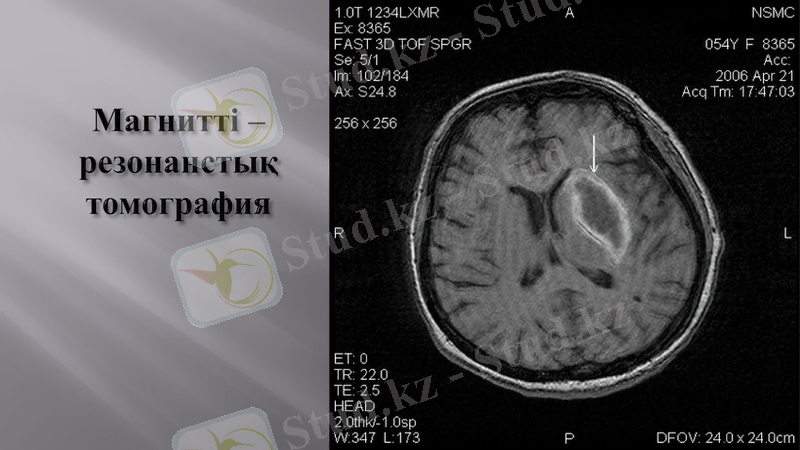

Компьютерлік томография- миға қан қүйылу мен ондағы ишемия ошақтарын ажырататын бірден бір аспап.

Магнитті - резонанстық томография- көлемі аса кіші қан құйылу ошақтарын, инсультке ұқсас басқа да ауруларды анқтайды.

Осы аспаптар арқылы алынған деректердің маңызы өте зор